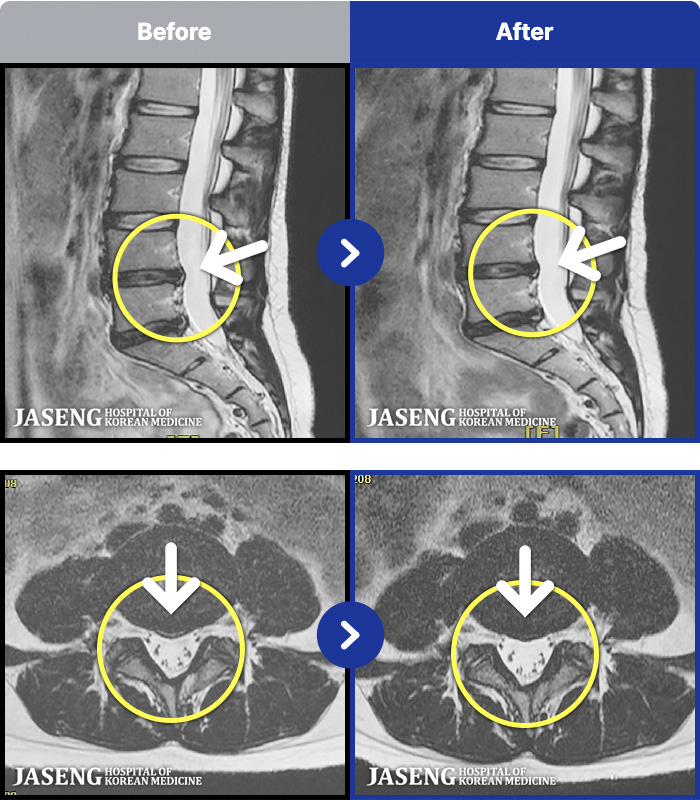

MRI ġ

56 MRI ũ ʸ Ȯϼ.